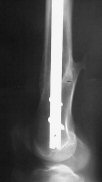

Отправитель: Enes M. Kanlic 13 Ноябрь 2004, 19:43

Attached are few examples from our Hospital:

A. Difficult reductions, even in retrograde nailing (my preference, easier control of "small" distal fragment) and it is much, much harder to do it anterograde (Alex, do you have one good case in your collection of anterograde nailing in very distal fractures - as you have suggested that I

should have done it in my previously posted case?

Malpositioning is much too common (recurvatum, varus - valgus).

B. Fixation loosening: distal cutting of the nail, non-unions do happen (cases attached).

Locking Plating has more distal screws than any nail, fixed angles and provides much better fixation, especially in osteoporotic bone.